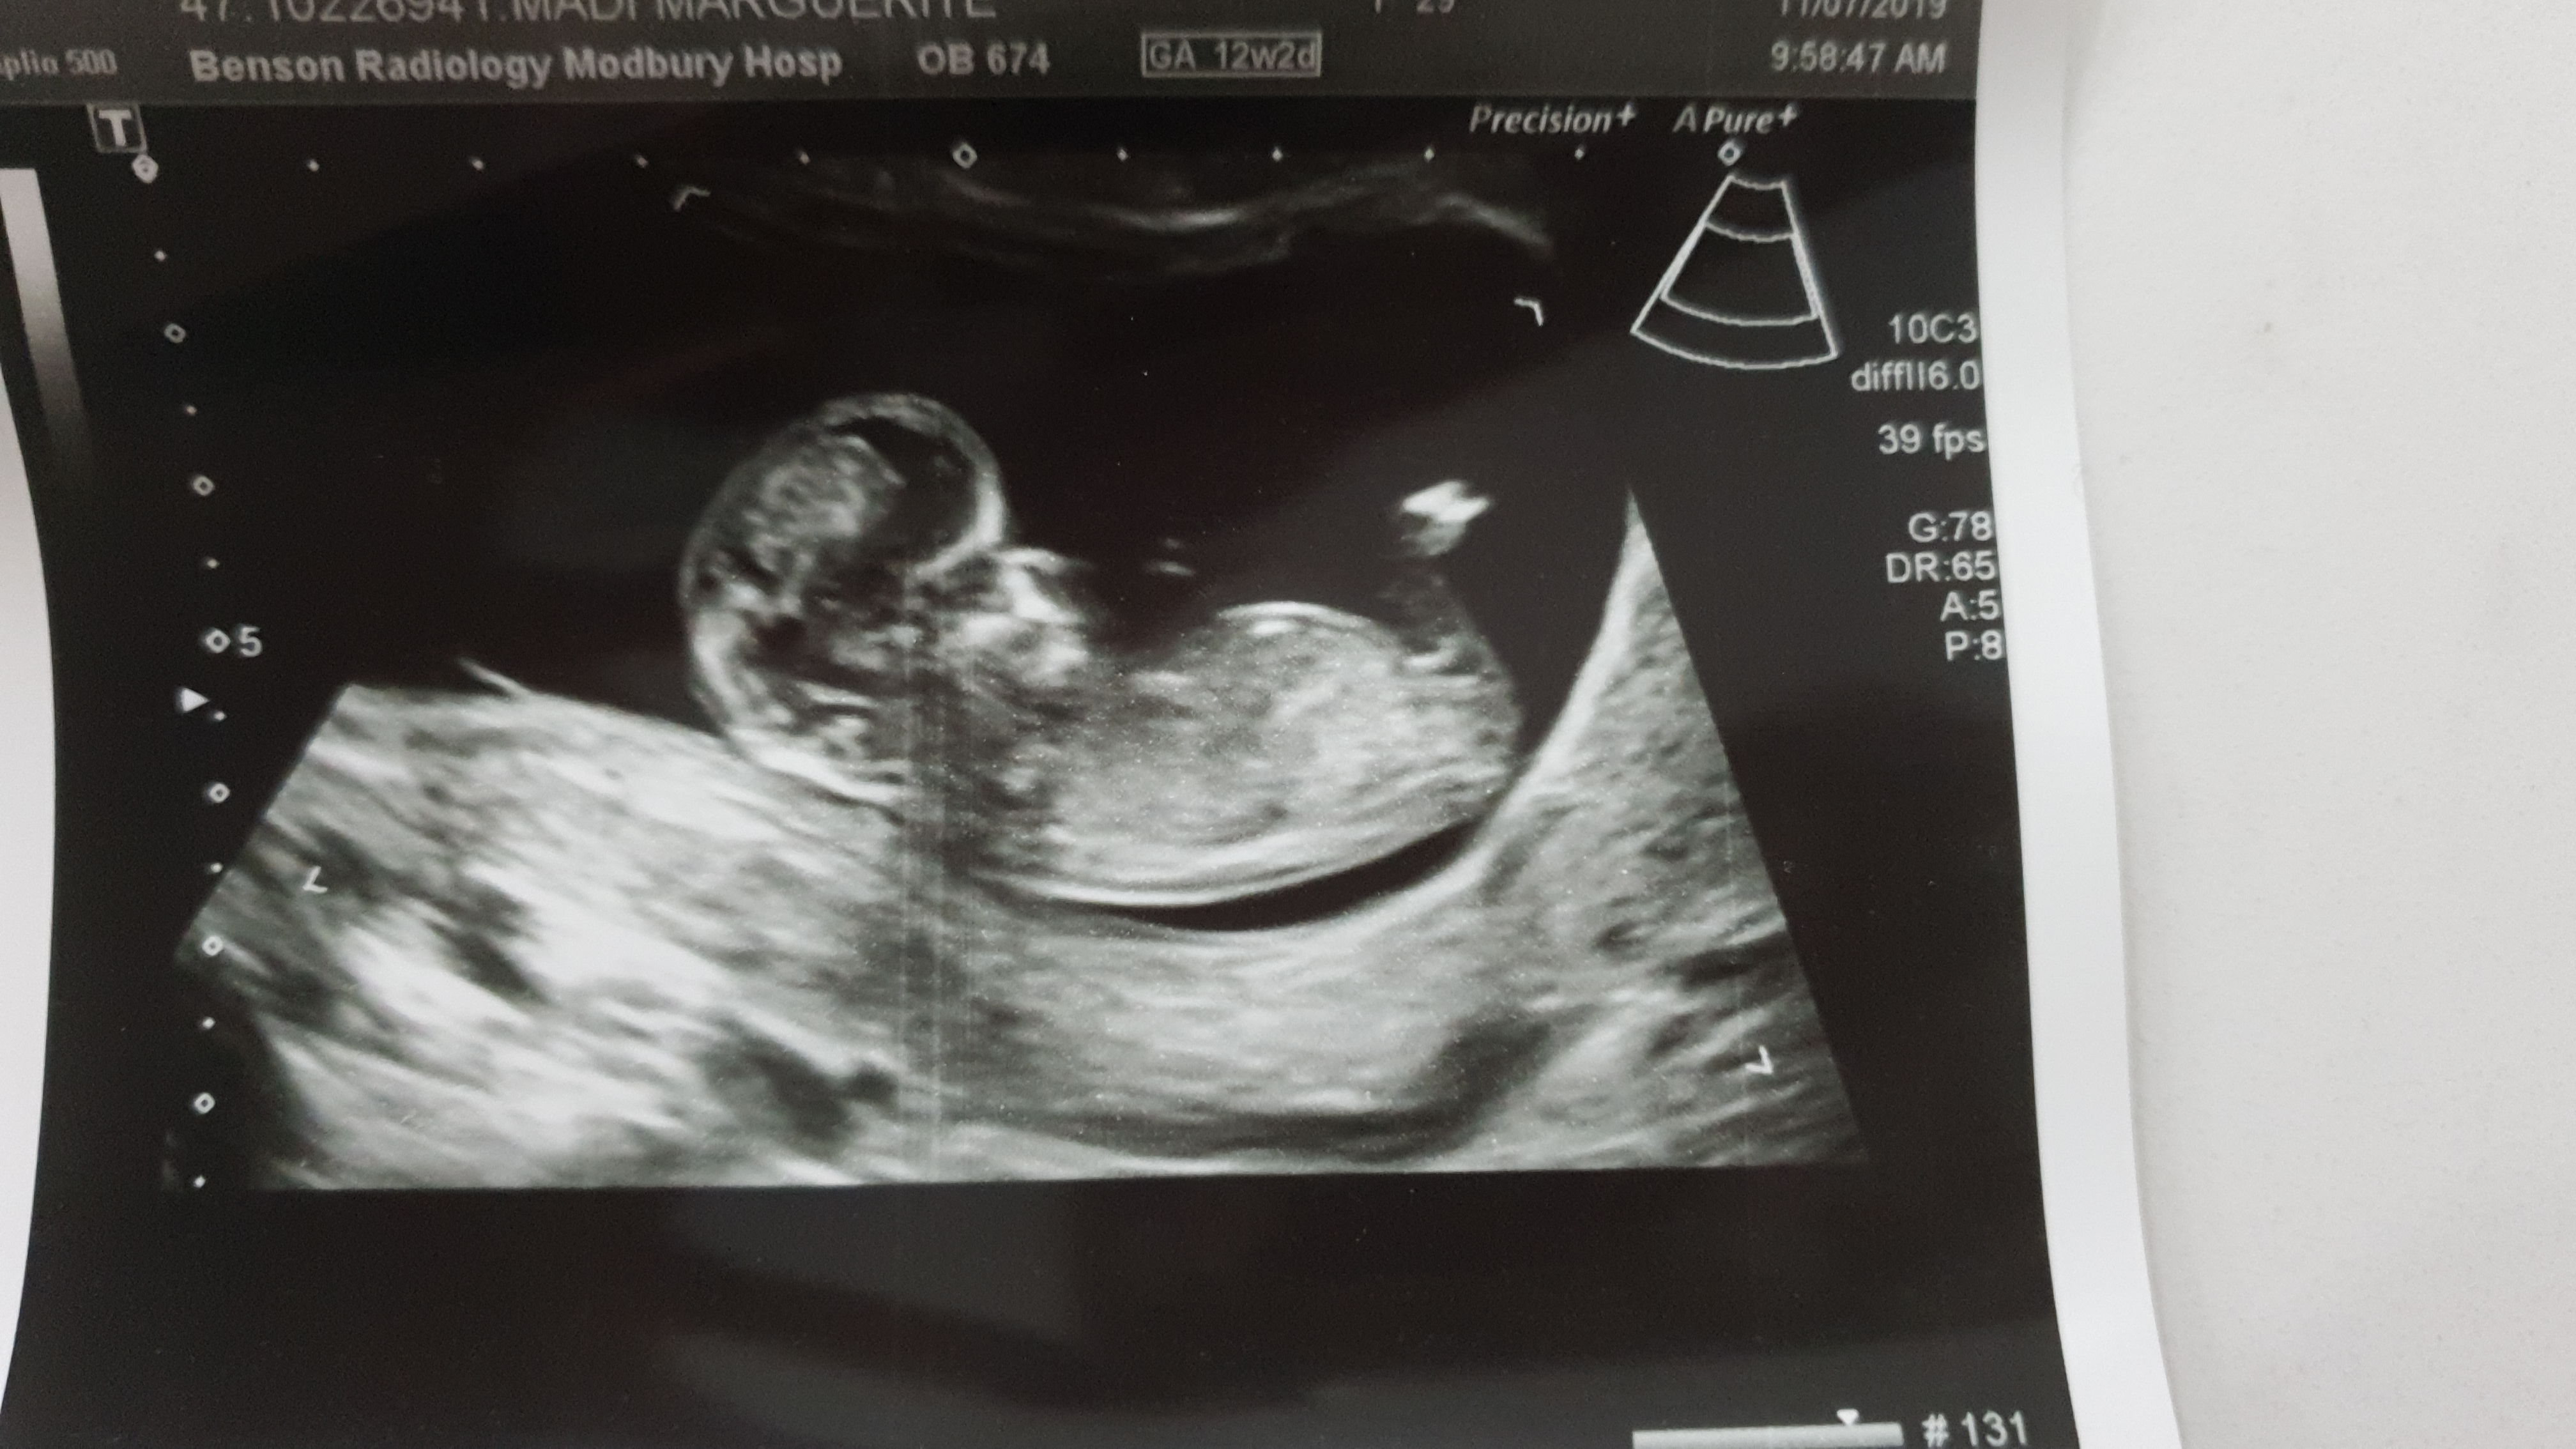

this is my 12 w 2 d scan , baby measure 11w 6 days.